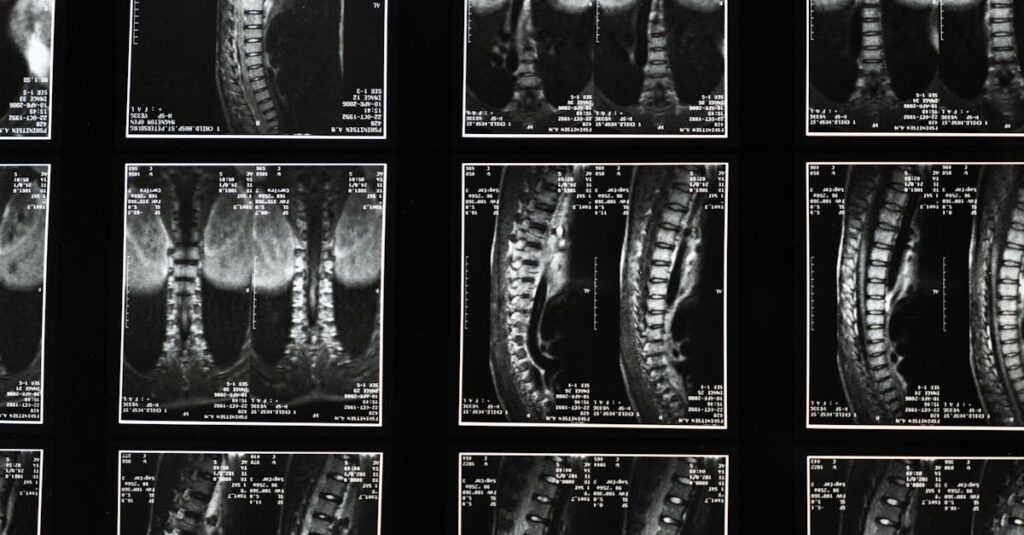

La sciatique résulte souvent de la compression ou de l’irritation du nerf sciatique. Cela peut être engendré par divers facteurs, notamment des hernies discales, une sténose spinale, ou encore des problèmes musculaires. La douleur, qui peut varier de légère à intense, peut impacter significativement la qualité de vie des personnes atteintes.

La sciatique se manifeste par une douleur intense qui irradie du bas du dos aux fesses, puis le long de l’arrière de la jambe. Cette douleur peut être causée par divers facteurs, notamment une hernie discale, une arthrose ou tout simplement une compression du nerf sciatique, résultant de mouvements brusques ou de mauvaises postures.

L’impact du surpoids sur la douleur sciatique

Le surpoids a des effets significatifs sur la mécanique du corps, et cela se traduit dans le cas de la sciatique. En effet, l’excès de poids génère une pression supplémentaire sur la colonne vertébrale et les articulations. Cet excès de tension peut compromettre l’intégrité des disques intervertébraux, augmentant le risque de hernie discale et de stenose spinale, des conditions qui sont souvent à l’origine de douleurs sciatiques.